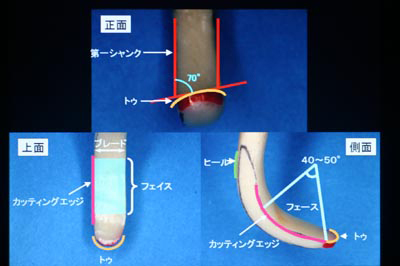

かわかみ実験:レントゲンでの骨頂線の安定のイメージ

さいとう実験:扁心投影でこれほど違ってみえる

これなど「よくもまあここまで、、、」といつもながら見る者を驚かさずにはおられない手の凝りようですが、レントゲンの規格性の重要さもよく理解できます。